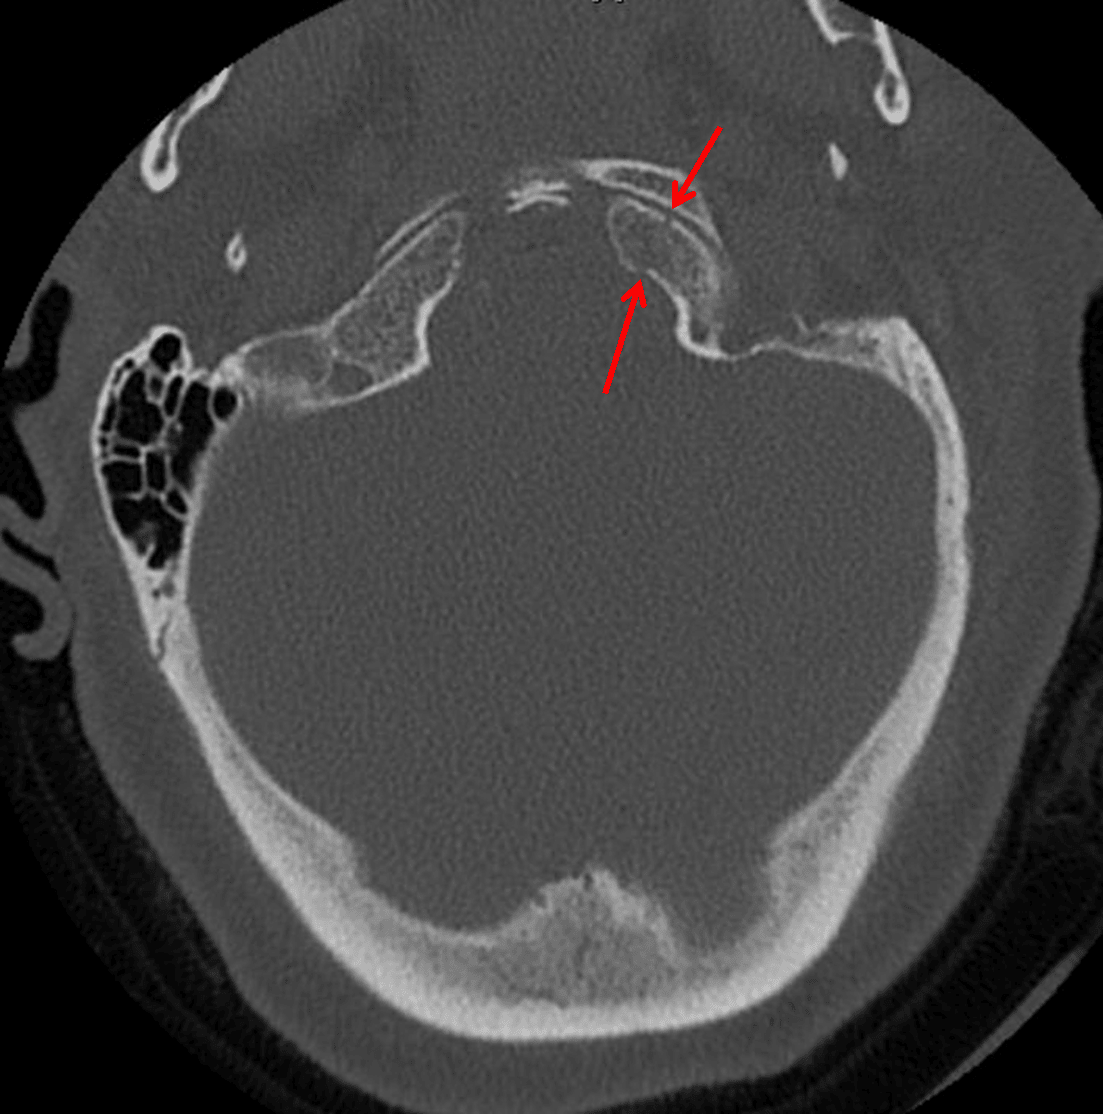

Red arrows: nondisplaced left occipital condyle fracture.

• Nondisplaced left occipital condyle fracture

Occipital condyle fracture

Acute nondisplaced left occipital condyle fracture. No traumatic malalignment.